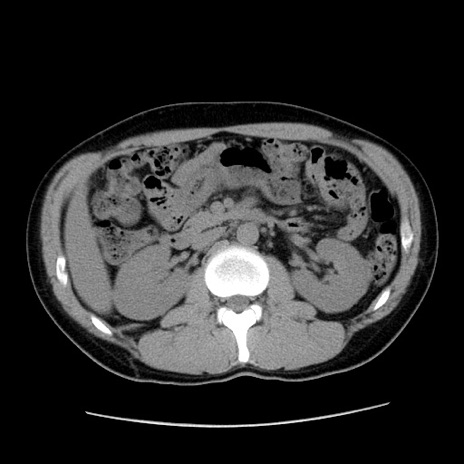

症例36(横断像)

【症例】20歳代 男性

【主訴】心窩部痛

【現病歴】今朝より上腹部痛あり。一旦軽快していたが再度出現したため救急要請。昨日夕に白身の魚を含む刺身を食べた。

【身体所見】BP 136/89mmHg、HR 74/min、BT 37.0℃、腹部:膨満、軟、心窩部に圧痛あり。反跳痛なし、筋性防御なし、腸雑音やや亢進あり。

【データ】WBC 17700、CRP 0.48